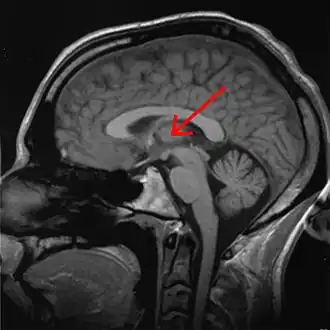

Thalamus marked (MRI cross-section)

Visual depiction of basic thalamus